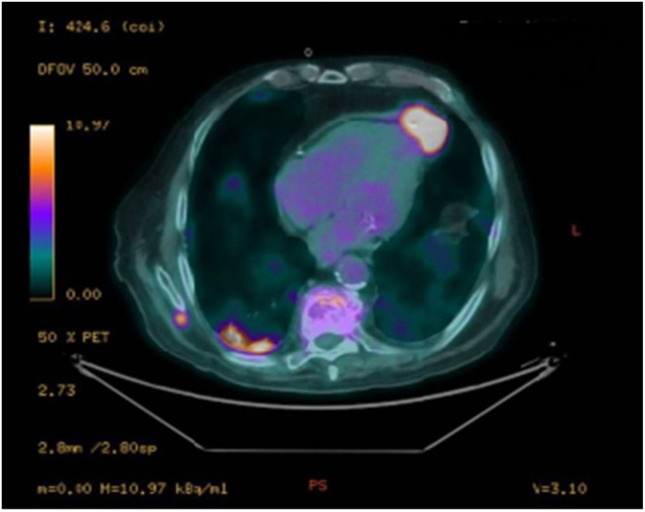

对症状性主动脉瓣狭窄的干预决策应权衡手术和经导管主动脉瓣植入术(TAVI)的风险。TAVI是一种成熟的技术,用于治疗老年和高危主动脉狭窄患者,采用多种不同的手术入路(逆行经股动脉、经腋窝、经主动脉或顺行经根尖入路)。经根尖入路需要心脏外科医生的参与,现在仅限于不能通过其他入路进行手术的病例。我们报告一例87岁的患者,患有严重外周动脉疾病,有经根尖入路TAVI病史,术后4年出现晕厥发作。影像学显示左心室顶动脉瘤,可能与先前的经根尖TAVI有关。该病例强调了在接受其他TAVI通路的患者中进行彻底的术前评估和长期随访的重要性,以及需要提高对罕见但重要的并发症(如心室假性动脉瘤)的认识。谨慎的患者选择和个性化的程序规划仍然是优化这一复杂人群结果的必要条件。

Decision-making for intervention in symptomatic aortic stenosis should balance the risks of surgery and of transcatheter aortic valve implantation (TAVI). TAVI is a well-established technique for treating elderly and high-risk patients with aortic stenosis using a variety of different surgical approaches (a retrograde transfemoral, transaxillary, transaortic or an antegrade transapical approach). The transapical approach requires the involvement of the heart surgeon and is now limited to cases where the procedure cannot be performed by alternative approaches. We report the case of an 87-year-old patient with severe peripheral arterial disease and a history of TAVI via transapical approach, who presented with a syncopal episode 4 years post-procedure. Imaging revealed a left ventricular apex aneurysm, likely related to the previous transapical TAVI. This case underscores the importance of thorough pre-procedural assessment and long-term follow-up in patients undergoing alternative TAVI access routes, as well as the need for heightened awareness of rare but significant complications such as ventricular pseudoaneurysm. Careful patient selection and individualized procedural planning remain essential to optimize outcomes in this complex population.